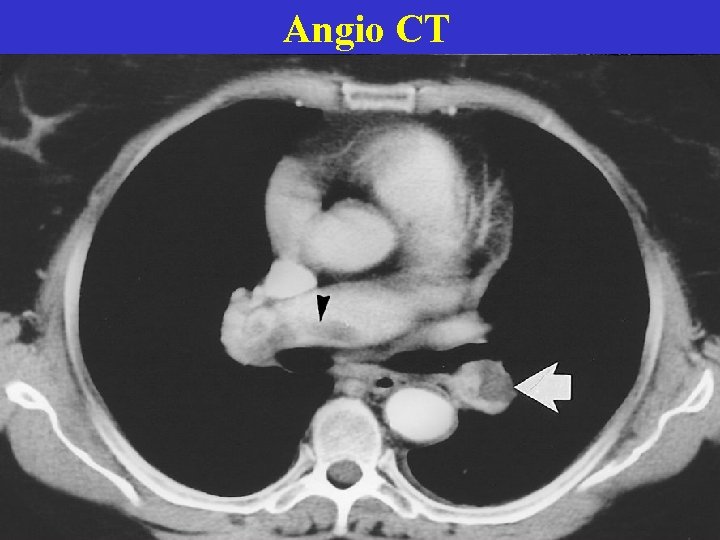

Angio CT